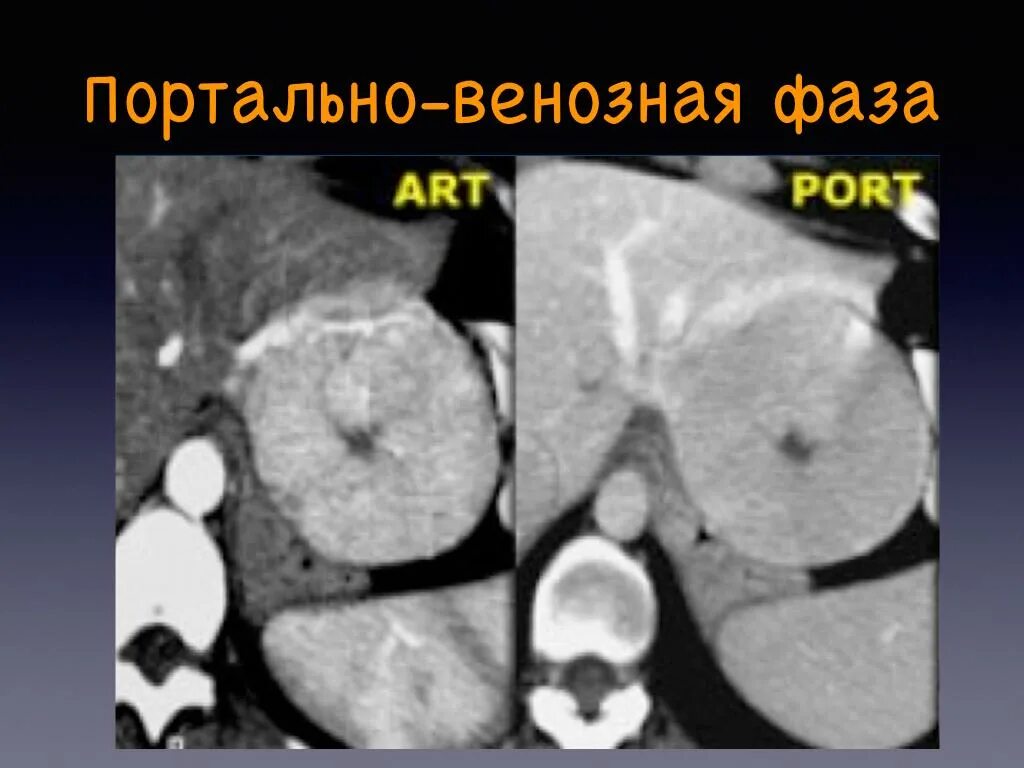

Фазы кт